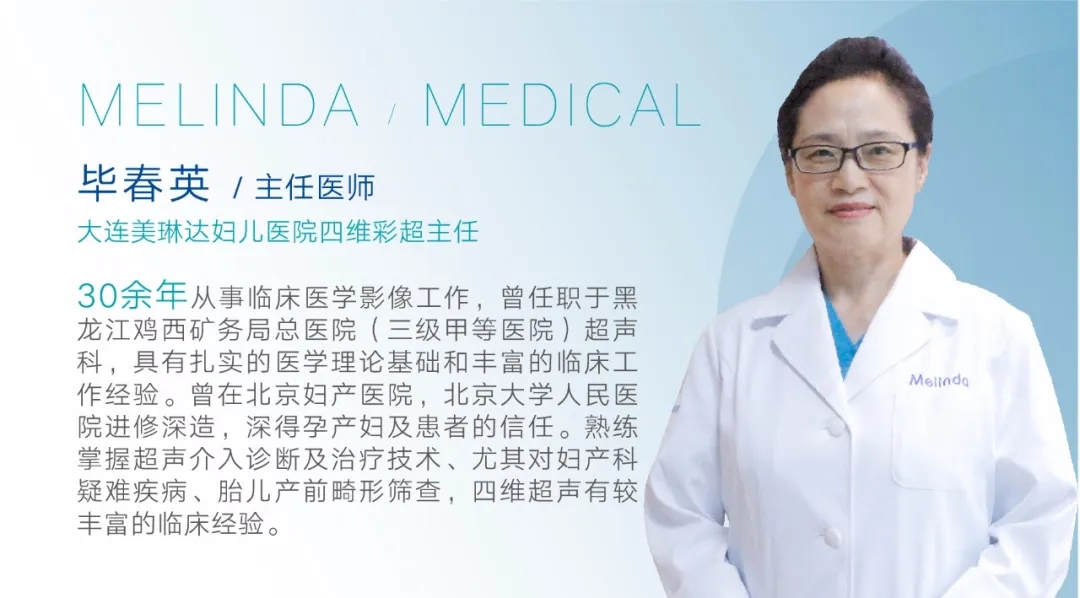

超声技术诊断精细-实力医生领衔团队美琳达超声科形成了以原大连大学附属中山医院妇产超声科主任,辽宁省超声医学工程学会妇产科委员会副主委,美琳达妇儿医院超声科首席医生杨光,以及原黑龙江省三甲医院超声科医生,美琳达四维彩超主任毕春英领衔的医生团队,他们均有丰富的妇产科超声诊断经验,在系统超声方面操作技能娴熟,检查仔细、(jing)准深受孕妈好评。